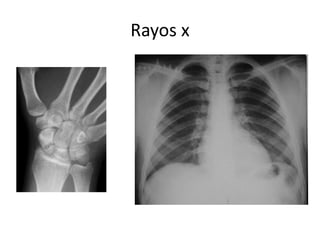

La anatomía humana se estudia utilizando diferentes técnicas como rayos X, tomografía y endoscopia que permiten ver el interior del cuerpo sin necesidad de cirugía. Estas herramientas médicas modernas proveen imágenes detalladas de los órganos y sistemas internos para diagnosticar enfermedades y guiar tratamientos mínimamente invasivos.